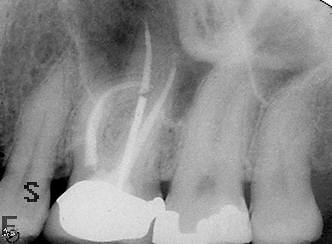

Excellent diagnosis essentially begins with two fundamental components: a doctor willing to listen to the patient’s chief complaint, and proper diagnostic tools. Among the most important tools are a precise periapical radiograph (PA) and bitewing (BW). Although a PA is often enough to provide an accurate portrayal of the patient’s condition, sometimes it alone does not suffice. Figure 1, Figure 2, and Figure 3 demonstrate a case that illustrates this point clearly. Despite two acceptable PAs (Figure 1 and Figure 2), it is difficult to assess the source of the patient’s pain to temperature. However, the BW radiograph Figure 3 provides significantly more clarity than either of the two PAs. The BW depicts localized bone loss (around tooth No. 2), a pulp stone (No. 2), a flat occlusion, numerous calcified canals, multiple restorations in tooth No. 30, and gross decay especially on tooth No. 3, which is the source of the patient’s pain to temperature. In this instance these images depict how much more useful a BW can be than just a conventional PA.

Fig 3. BW of the same upper right area as shown in Figure 1 and Figure 2, depicting gross decay not visualized on prior PAs.

Figure 3